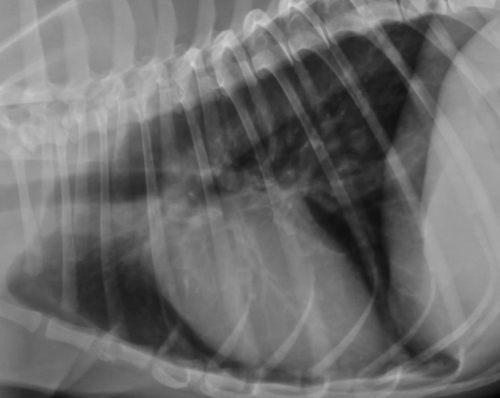

下のレントゲン写真が巨大食道症の一例で、黄色矢印の先に飲み込んだ空気によって拡張した食道壁を示す特徴的な白いラインが見えます。右下が正常の胸部レントゲン写真です。